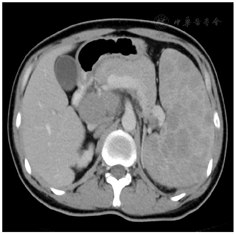

血常规检查WBC 1.72×109/L、HGB 99 g/L、PLT 62×109/L,凝血功能检查正常,CD4计数100 cells/ul,血β微球蛋白4.98 mg/L,EB-DNA3470 Copies/ml,HBV-DNA低于100 IU/ml,HCV-RNA1 480000 IU/ml,丙肝基因分型6n亚型。AST35 U/L、ALT18 U/L、LDH493 U/L。腹部CT检查提示脾脏肿大,多发占位病变(图2),在B超定位下行经皮脾脏穿刺活检。同时骨髓检查细胞学为增生减低骨髓象,骨髓活检提示增生不均一,三系增生可,未见明显异型细胞。淋巴瘤/淋系白血病相关CD系列检测提示送检标本中T淋巴细胞CD4:CD8比值明显减小。骨髓染色体核型46,XY,未见克隆性数目及结构异常。